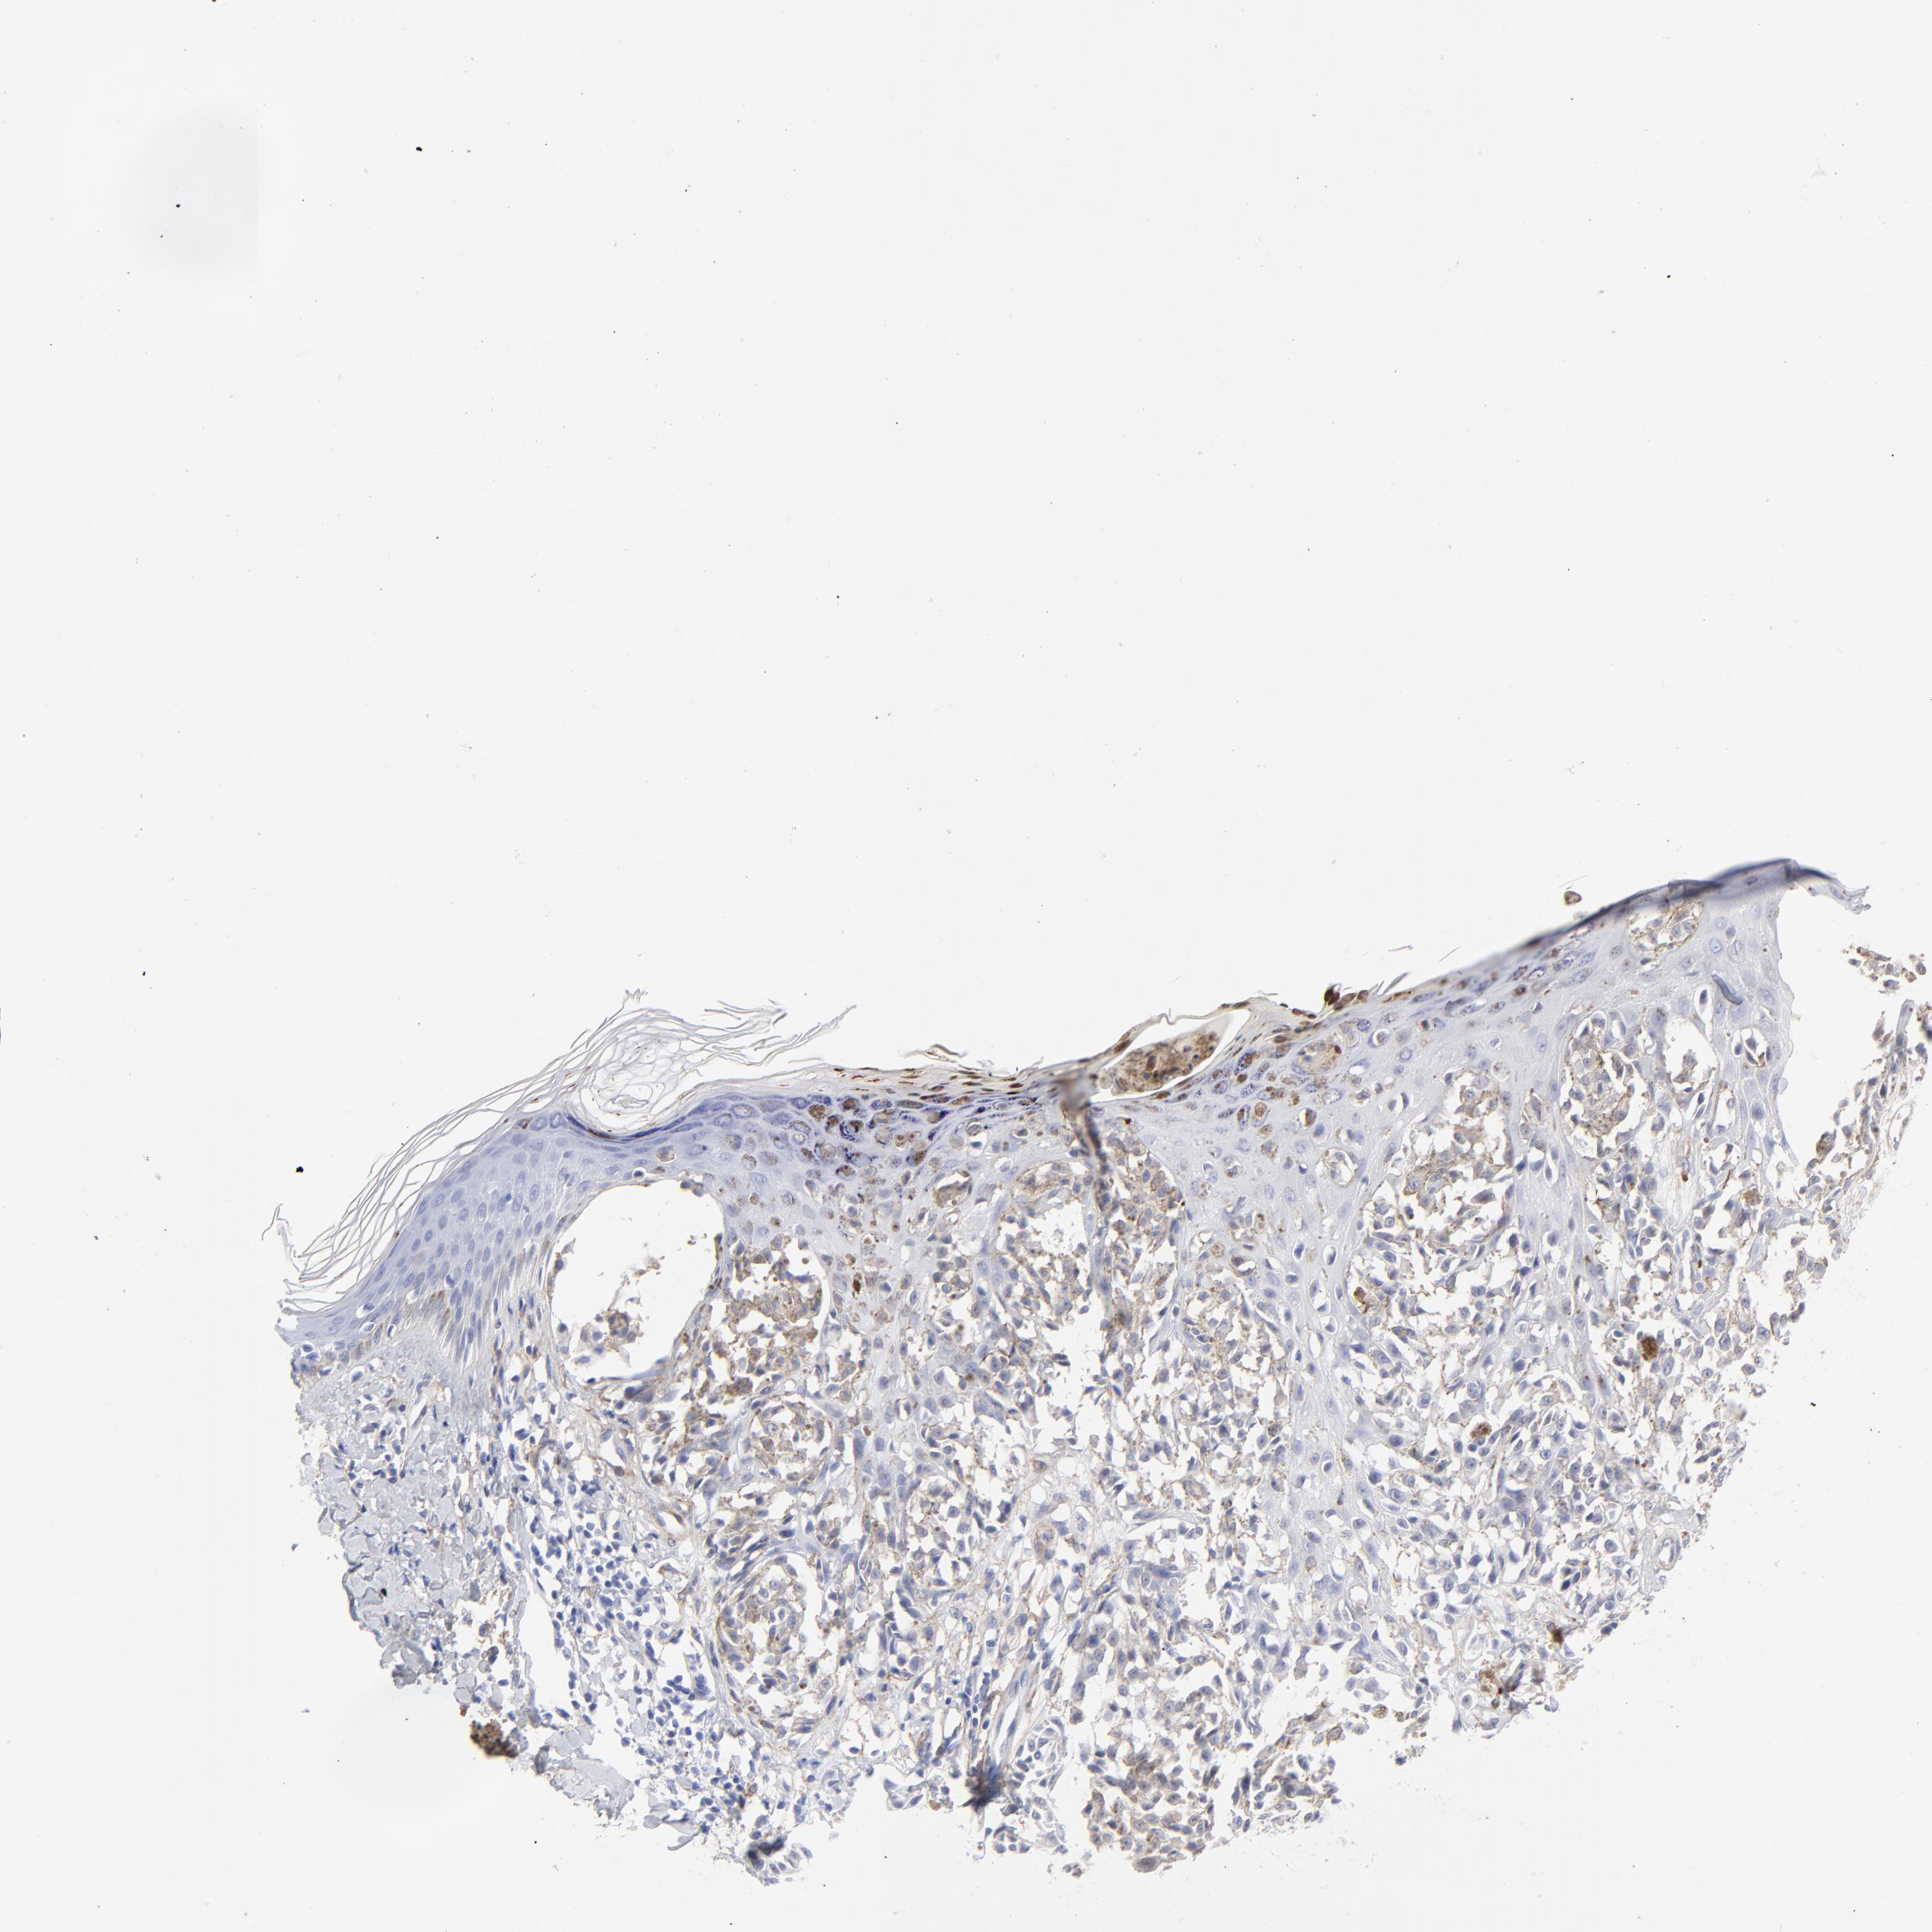

MELANOMA - Protein expressioni

A mouse-over function shows sample information and annotation data. Click on an image to view it in a full screen mode. Samples can be filtered based on level of antibody staining by selecting one or several of the following categories: high, medium, low and not detected. The assay and annotation is described here.

Note that samples used for immunohistochemistry by the Human Protein Atlas do not correspond to samples in the TCGA dataset.

Antibody stainingi

Antibody staining in the annotated cell types in the current human tissue is reported as not detected, low, medium, or high, based on conventional immunohistochemistry profiling in selected tissues. This score is based on the combination of the staining intensity and fraction of stained cells.

Each image is clickable and will lead to virtual microscopy that enables deeper exploration of all samples and also displays staining intensity scores, fraction scores and subcellular localization as well as patient and tissue information for each sample.

Antibody CAB003842

Antibody CAB018144

Staining

High

Medium

Low

Not detected

Intensity

Strong

Moderate

Weak

Negative

Quantity

>75%

75%-25%

<25%

None

Location

Nuclear

Cytoplasmic/membranous

Cytoplasmic/membranous,nuclear

Malignant melanoma, NOS

Malignant melanoma, Metastatic site